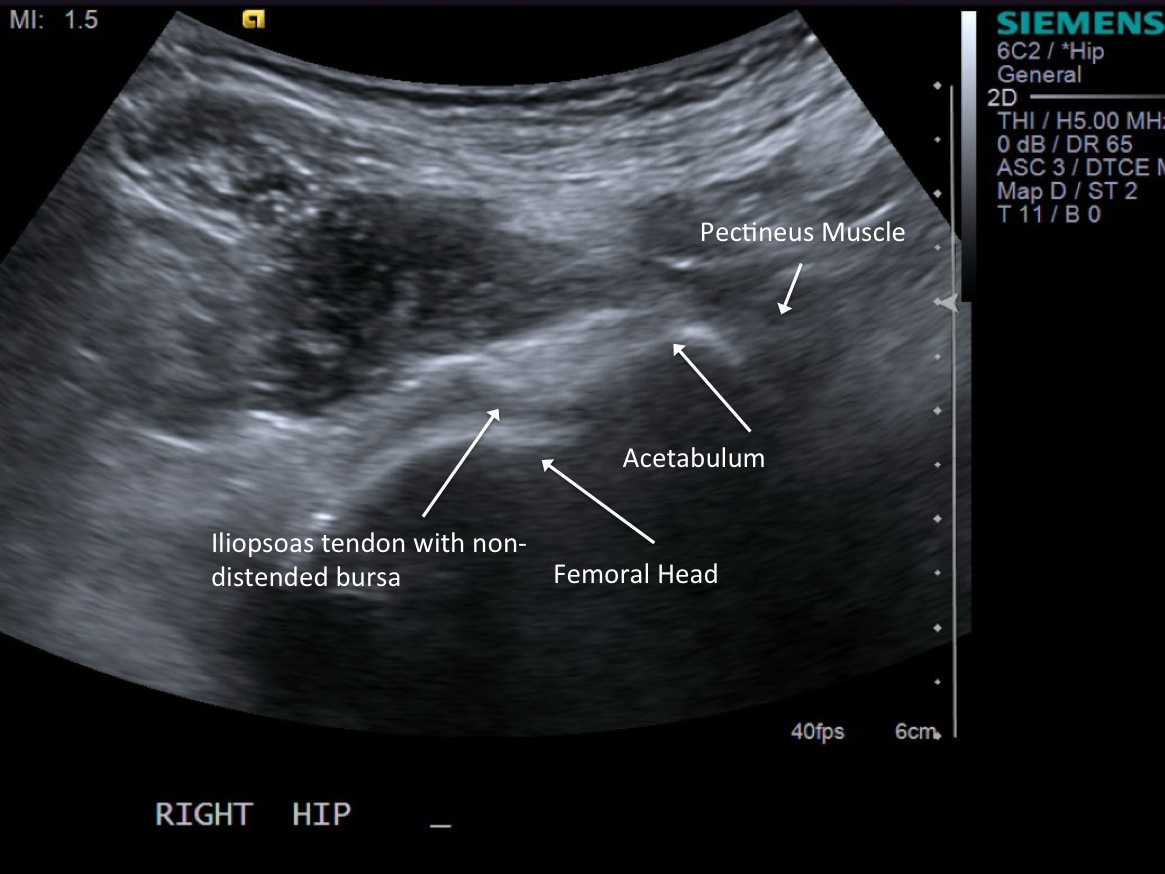

2.Position patient supine.

• descriptiondescription

Transverse/short axis view of iliopsoas tendon